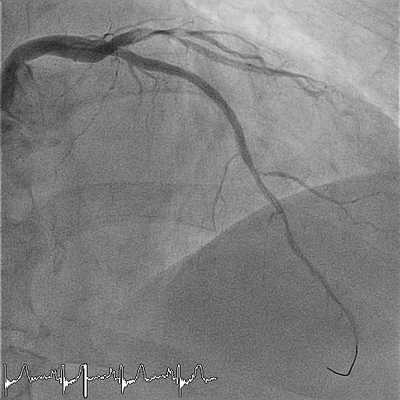

![Коронография - лучший метод диагностики поражений сосудов сердца]()

Контрастное вещество вводится в кровеносные сосуды сердца. Затем рентгеновский аппарат делает серию снимков (ангиография), показывая проходимость этих коронарных артерий. Это исследование позволяет определить причину ишемии миокарда и принять меры для нормализации кровотока по коронарным артериям.